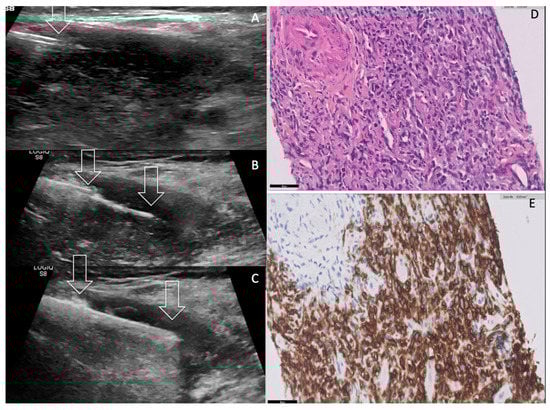

| Imaging Features US Doppler EuTIRADS score IJV invasion Computed Tomography | Reticular pattern More homogeneous than thyroid carcinoma No necrosis/calcification Sword sign Eu-TIRADS 5 Rare No cystic necrosis No gross calcification Homogeneous Nodes +/0 Mild vasculature Unclear boundaries + Vessel invasion not usual Tracheal compression + | No reticular pattern Heterogeneous Necrosis /calcification Sword sign Eu-TIRADS 5 Not rare Cystic necrosis Gross calcifications Heterogeneous Nodes ++/− Few vessels Unclear boundaries ++ Vessel invasion (33%) Tracheal compression ++ | No reticular pattern Inhomogeneous Depends on pre-existing thyroid No Sword sign Eu-TIRADS 5 > Eu-TIRADS 4 Exceptional No cystic necrosis No gross calcification Nodular Nodes +/− Increased Vasculature (renal) Unclear boundaries 0/+ Vessel invasion very rare (renal) Tracheal compression 0/+ |